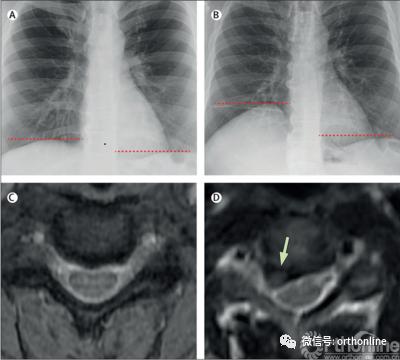

2020年10月Lancet的Clinical picture[2]报道了一例典型的由颈椎病导致呼吸困难的病例。患者是一名50岁男性,突发呼吸短促及右肩后侧疼痛,无任何颈部疼痛、四肢麻木及无力表现。胸部X线提示右侧膈肌抬高(图B),颈椎MRI提示C3-C4椎间盘突出导致右侧C4神经根严重压迫(图D)。在该院行C3-C4的颈椎前路减压融合术(anterior cervical decompression and fusion, ACDF)后,患者的肩痛症状和呼吸困难明显改善。术后随访X线提示患者右侧膈肌恢复到基本正常的高度。

图1:A.2年前胸片. B.术前胸片. C.2年前C3-C4椎间隙MRI. D术前C3-C4椎间隙MRI